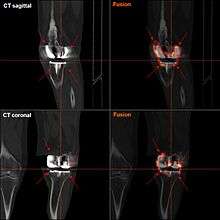

According to a recent review the following tests can be used in the diagnosis of a periprosthetic infection.[11]

- Conventional radiograph: Rule out other conditions such as loosening and/or osteolysis.